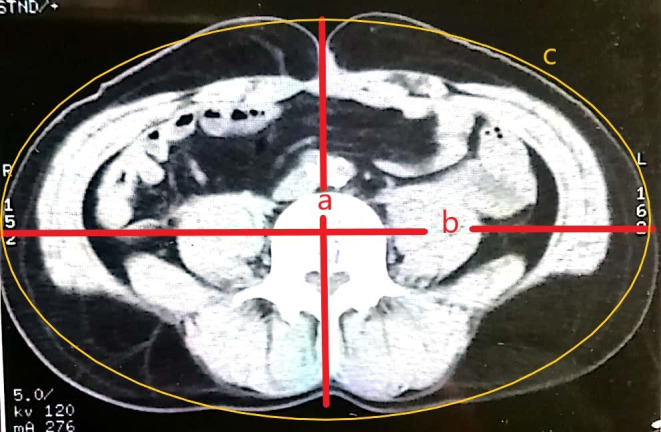

Results: We developed a prototype of the app Measure It, which is capable of estimating WC from a single cross-sectional CT image. We used an estimation based on an ellipse formula adjusted to the gender of the patient. The validity study included 20 patients (10 men and 10 women). There was a good correlation between both measurements (Pearson R=0.906). The student t test showed no significant differences between the two measurements (P=.98). Both the Q-Q dispersion plot and Bland-Altman analysis graphs showed good overlap with some dispersion of extreme values. The diagnostic test evaluation showed an accuracy of 83% when using the mobile app to detect abdominal obesity.